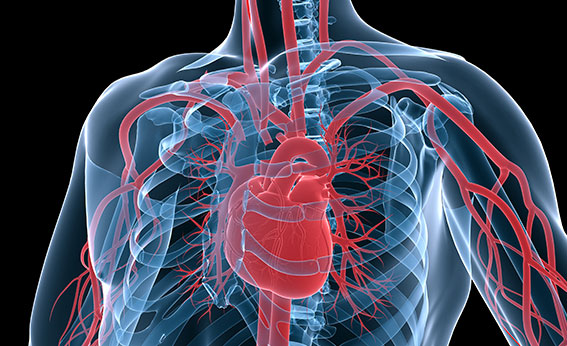

가슴이 좁아지는 듯한 느낌과 통증을 느끼기 때문에 협심증이라 불러요. 협심증은 심장에 혈액을 공급해주는 관상 동맥이 좁아져 충분한 혈액공급이 이루어지지 않아 발생되는 가슴통증을 말하는 질환인데요. 관상동맥이 좁아지는 동맥 경화증은 20대 초반부터 시작되며 혈관이 약 70% 이상 좁아지면 협심증 증상이 발생하게 됩니다.

협심증이란 관상동맥에 경화가 일어나면서 발생하는 증상인데요. 동맥경화는 혈관에 지방 등이 쌓이면서 혈관이 좁아지게 되어 혈관 탄력성을 잃게 되는 것입니다. 혈관이 심장이 뛰는 것에 맞춰서 확장과 수축을 반복하면서 혈류가 이동하게 되는데 이 때 혈관에 플라크가 지방이 축적이 되면 혈류의 이동에 방해를 받게 된다고 해요.